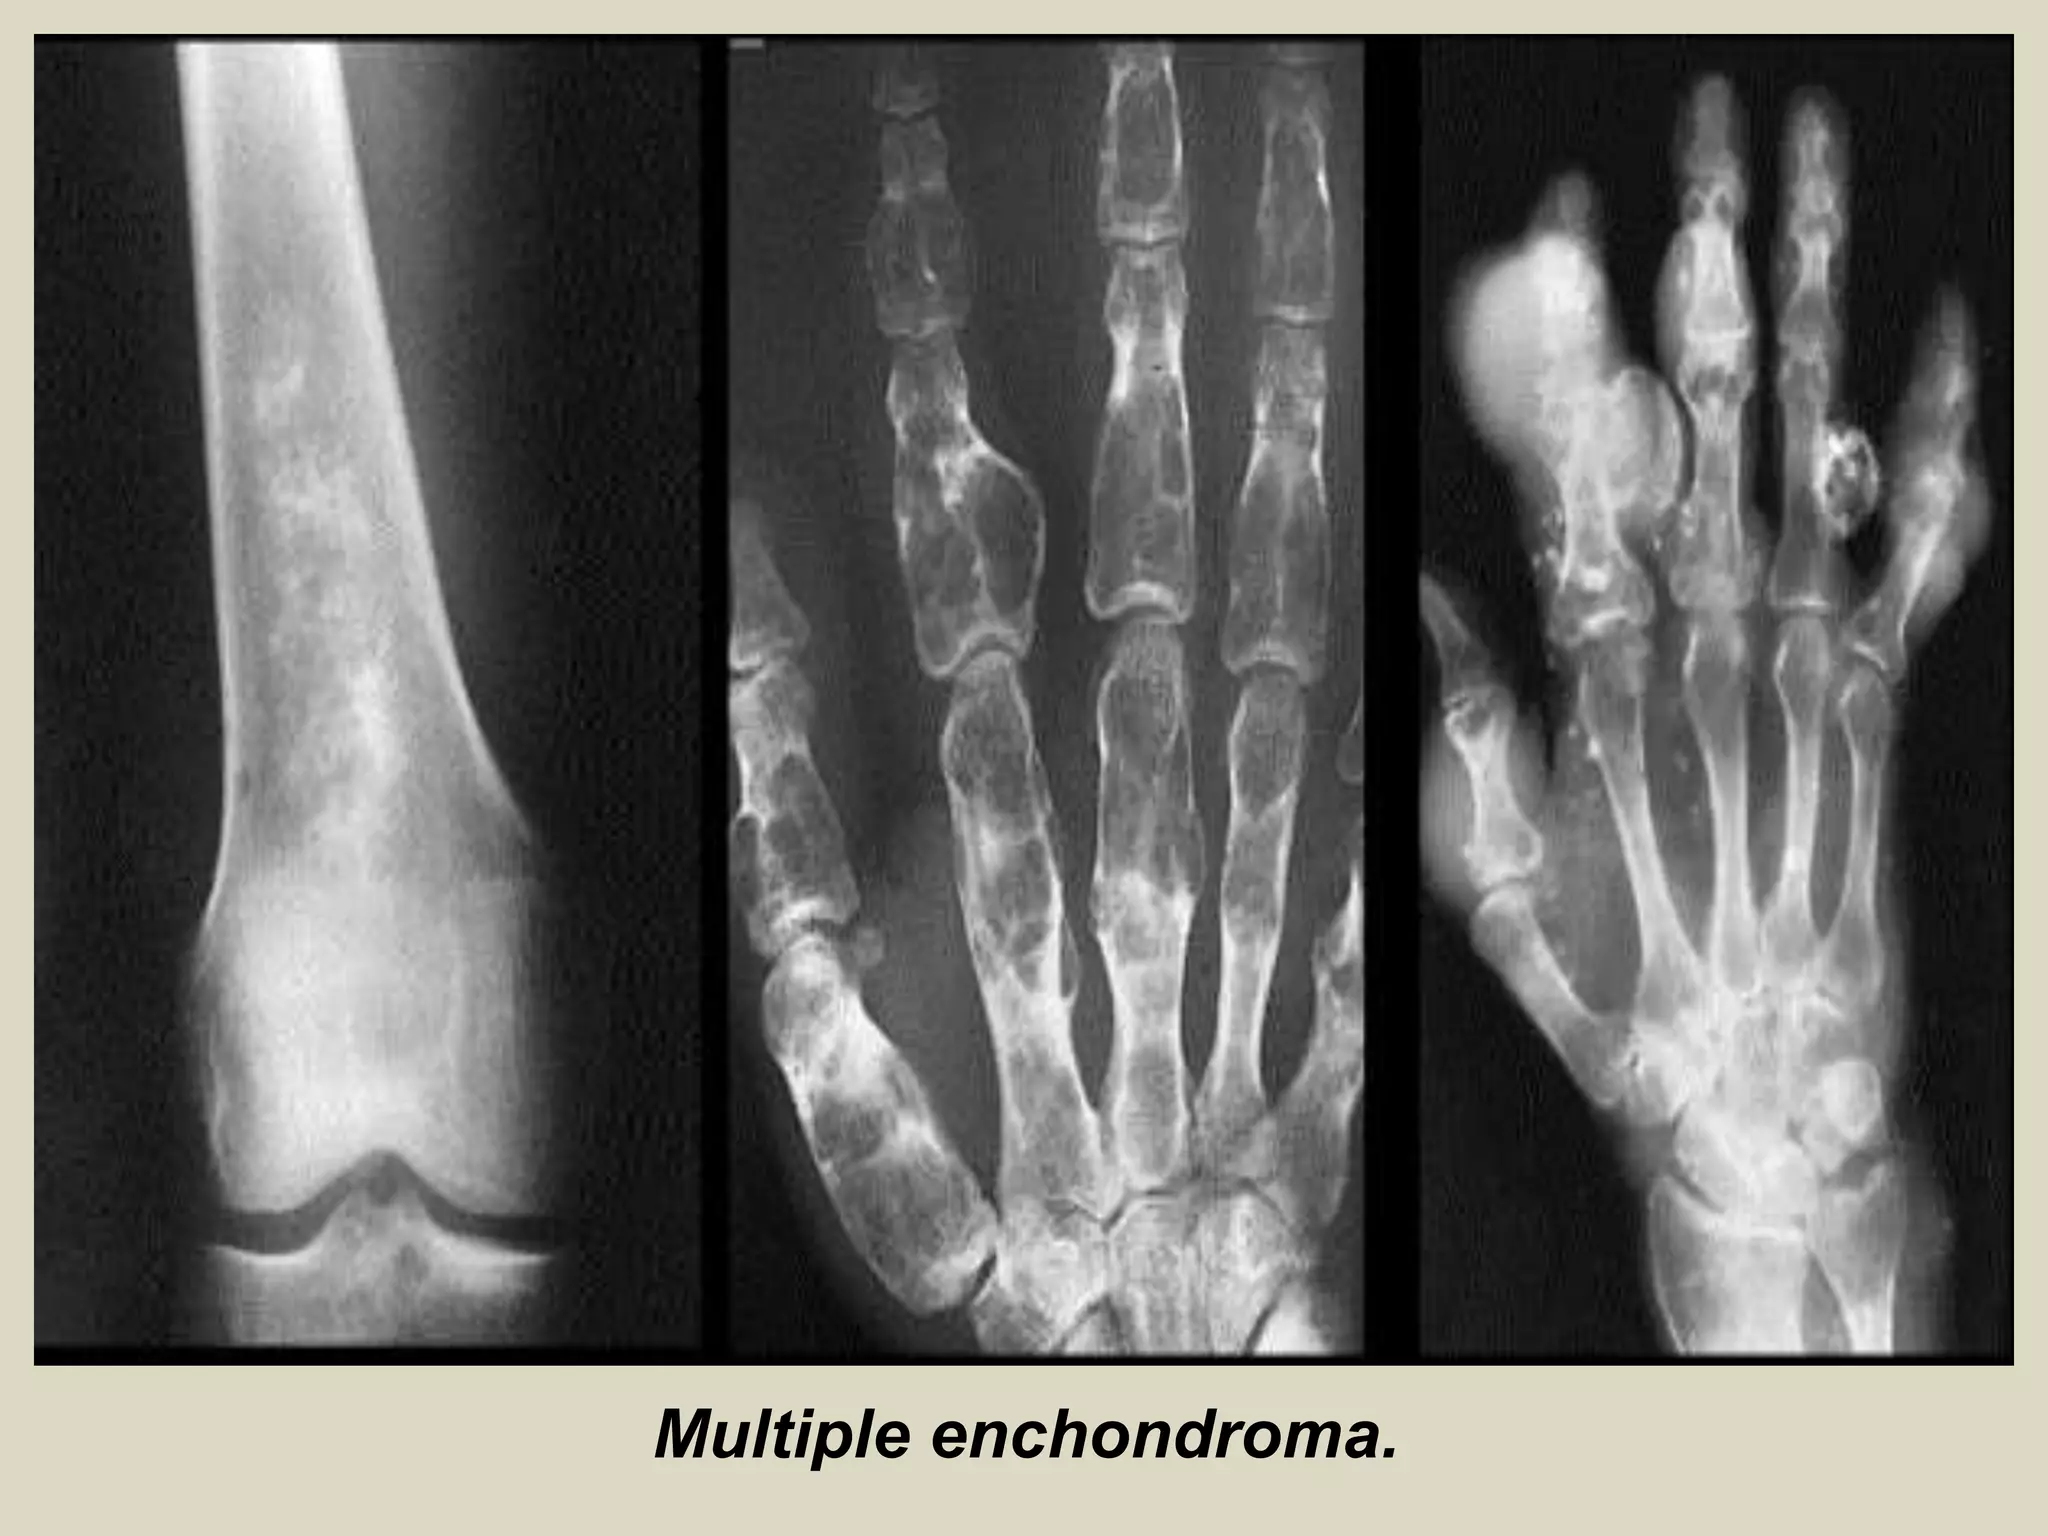

ENCHONDROMA AND ENCHONDROMATOSIS

Definition: Benign hyaline cartilage neoplasm of medullary bone.

- Enchondromatosis, is defined as two or more enchondromas, and occurs in two clinical settings: 90% are

associated with Ollier disease (two or more enchondromas) 10% are seen in Maffucci syndrome

Sites of involvement: Usually metaphyseal-diaphyseal in location and frequently affect the short tubular bones of the hands.

- Followed by bones of the feet and the long tubular bones, especially proximal humerus and proximal and distal femur.

Imaging:

- Well marginated tumors that vary from radiolucent to heavily mineralized.

- Mineralization pattern is characteristic, consisting of punctate, flocculent, or ring and arc pattern.

- Long bone tumors are usually centrally located within metaphysis.

- Diaphyseal long bone tumors are less common, and epiphyseal tumors are rare.

- Enchondromas in the small tubular bones can be centrally or eccentrically located, and larger tumors may

completely replace medullary cavity.

- More extensive endosteal erosion is considered suspicious for low grade chondrosarcoma.

- Cortical destruction and soft tissue invasion should never be seen in enchondromas and would be most

consistent with chondrosarcoma.

Multiple enchondroma.